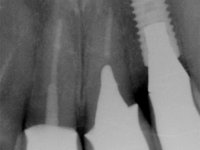

Endodontic treatments were performed and a metalic non screwed intra radicular post was placed on tooth 1.1. An alginate impression was made for laboratory confection of a reinforced acrylic provisional bridge, with teeth 1.1 and 2.2 as abutments and 2.2 as a pontic. After preparation of tooth 1.1 and root preparation of 2.1, the bridge was relined in mouth with self-polymerizable acrylic using a metal post for further retaining the prepared root canal on 2.1. Tooth 2.2 was cut at the gingival level to function as support. In the same session, the impression of the root canal of the 2.1 was made for the laboratory confection of a cast post and core. A double mixture technique with plastic tutor was used after previous canal vaseline with endodontic file and cotton. The provisional bridge was provisionally cemented and the cast post and core was made in the laboratory. Cast post and core cementation was made with resin-reinforced glass ionomer cement and the provisional bridge had to be readjusted to the new situation by removing the post at the site of 2.1. After careful surgical planning, a dental implant was placed, simultaneously with extraction of the root of tooth 2.2. The provisional bridge was placed by resting on the healing screw placed in the implant. The respected osteointegration period was 12 weeks, during which the provisional bridge was relined twice. After complete maturation of hard and soft tissues, definitive impressions were made. The gingival retraction technique was applied with an impregnated retraction cord and impression was performed using double mixture, open tray impression technique. A custom precious metal abutment implant was prepared in the lab, along with 3 metal caps to be used as infrastructures for the metal ceramic crowns. Particular care was taken in the confection of the cervical finishing line of the implant abutment, in order to follow the soft tissues emergence profile. Proof of infrastructures was done in the mouth being evaluated clinically and imagiologically. Collection of color information was done by the ceramist at the office. Ceramic was applied in the laboratory and the finished work was placed in the mouth after approval by the patient. Definitive cementation was made with resin-reinforced glass ionomer cement, and the first crown to be cemented was that of the implant, to facilitate removal of the excess.